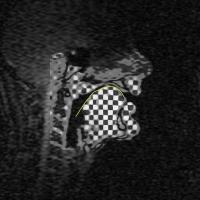

tMRI of "ku" (grid of tags)

tMRI of /i/-/a/ (MICSR). |

/i/-/a/ composite of two data sets:

/i/-/a/ composite of three data sets:

How MICSR works |